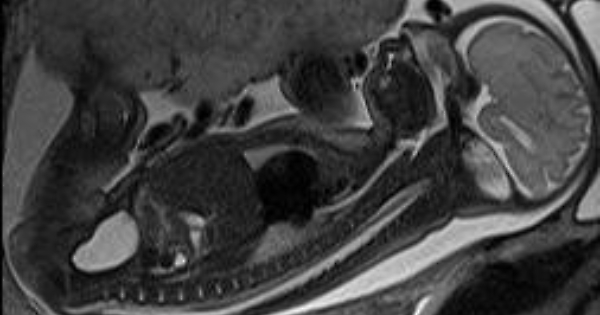

Roma, 28 apr. (AdnKronos Salute) - La tutela della salute inizia nell'utero materno. Al D'Amore Hospital di Taranto è stata eseguita per la prima volta una risonanza magnetica fetale per rintracciare una sospetta patologia cerebrale già diagnostica, su un feto di 19 settimane. E' stata l'équipe di Radiologia, guidata da Maurizio Resta, specializzato nella diagnosi e nel trattamento di patologie in ambito neurologico, a effettuare il delicato esame. "La diagnosi ecografica - spiega Resta - ha accertato una sospetta condizione patologica al cervello del feto e la risonanza magnetica ha chiarito la natura di tale malformazione: questo ha consentito di pianificare il miglior percorso di terapia". "La risonanza magnetica ha assunto un ruolo sempre più cruciale nella determinazione delle anomalie del sistema nervoso fetale, anche in utero - precisa Resta - Diventa fondamentale per il radiologo quando il bebè è ad alto rischio di sviluppare un deficit neurologico". Il principale campo di applicazione della risonanza magnetica fetale riguarda lo studio delle malformazioni del cervello, ma non solo: l'indagine si estende anche alla valutazione delle patologie di collo, torace, apparato gastroenterico e apparato uro-genitale, e di recente anche al cuore fetale. L'esame diagnostico di secondo livello, che sfrutta il campo magnetico, rappresenta infatti un utile complemento alla tradizionale ecografia: è piuttosto articolato perché studia un organismo contenuto nell'utero, analizzando ogni aspetto di un'entità biologica presente in un'altra. "La difficoltà principale nell'esecuzione materiale - prosegue Resta - dipende dalla necessità di inseguire un feto che tende a muoversi. L'esame inoltre è limitato dalle ridotte dimensioni delle componenti anatomiche da indagare". Si tratta tuttavia di un'indagine sicura. "Non ci sono evidenze scientifiche su eventuali danni al bambino dall'esecuzione della risonanza magnetica. L'esame utilizza un campo magnetico e radiofrequenze e non radiazioni ionizzanti, al contrario di quanto accade nella Tac - continua Resta - Le tecniche non invasive di diagnosi prenatale sono andate migliorando sempre più negli ultimi anni, e questo ha consentito di raggiungere risultati più precisi riducendo eventuali rischi causati da emissioni radioattive". Grazie ad apparecchiature all'avanguardia e alla recente introduzione di nuove tecniche di imaging, la Radiologia del D'Amore Hospital si accredita così a centro di riferimento regionale per la prevenzione e la diagnosi di malformazioni fetali attraverso esami specifici di alta complessità in grado di tutelare la salute dei bambini già nell'utero materno. Resta, neuroradiologo di fama internazionale, affiancato da Massimo Donatelli, grazie a una esperienza maturata negli anni anche all'estero, si sono specializzati nell'attività diagnostica che rintraccia precocemente le principali patologie neurologiche, oggi tanto diffuse come ictus, aneurismi e malformazioni arterovenose. Gli specialisti mettono in pratica le metodiche più moderne, come ad esempio la spettroscopia, o la perfusione di risonanza magnetica sul cervello, in grado di individuare anche formazioni neoplastiche di dimensioni molto ridotte.